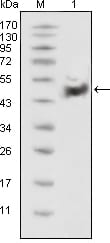

分类: 科研抗体货号: 20338别名: LFS1, TRP53, TP53应用: WB,IHC反应种属: Human

-